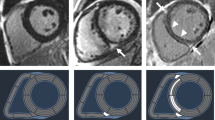

Cardiac magnetic resonance

CMR examinations were performed at the time of the inclusion on a 3.0-T scanner (Magnetom Skyra, Siemens, Erlangen, Germany). CMR studies were analysed by using Syngo.VIA software version VB 40 (Siemens, Erlangen, Germany) following the post-processing guideline from the Society of Cardiovascular Magnetic Resonance7,8. Steady-state free precession cine images were obtained in consecutive short-axis slices covering the LV and three long-axis (2-, 3-, and 4-chamber) slices. The CMR protocol included cine CMR, native and post-contrast T1 mapping, and LGE imaging. The LV was divided into 16-segment model described by the American Heart Association. Cardiac volumetric and functional parameters were quantified based on manual delineation of the endocardial and epicardial borders using a stack of continuous short-axis slice cine images.

Assessment of replacement fibrosis

Consecutive short-axis LGE images covering the LV were obtained 15 min after intravenous injection of 0.1 mmol/kg of body weight gadolinium-based contrast agent. The presence of LGE was judged by three independent observers blinded to patients’ information (M.U., M.K. and M.M.). Fibrosis was considered present if LGE was visualized on both short- and orthogonal long-axis LGE images. The quantitative analysis of LGE extent was assessed using 5 standard deviations threshold on consecutive short-axis slices and calculated as a percentage of total LV mass (%LGE) (Fig. 3)7,8.